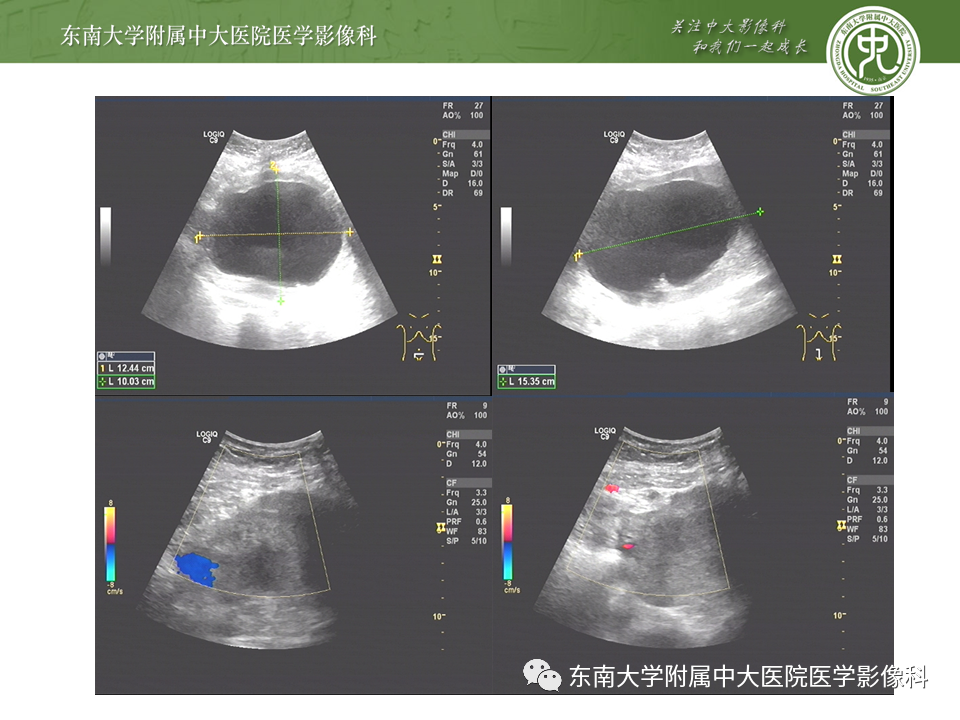

病史

女,24岁,因“停经42天,下腹痛3小时”入院

影像学表现

超声